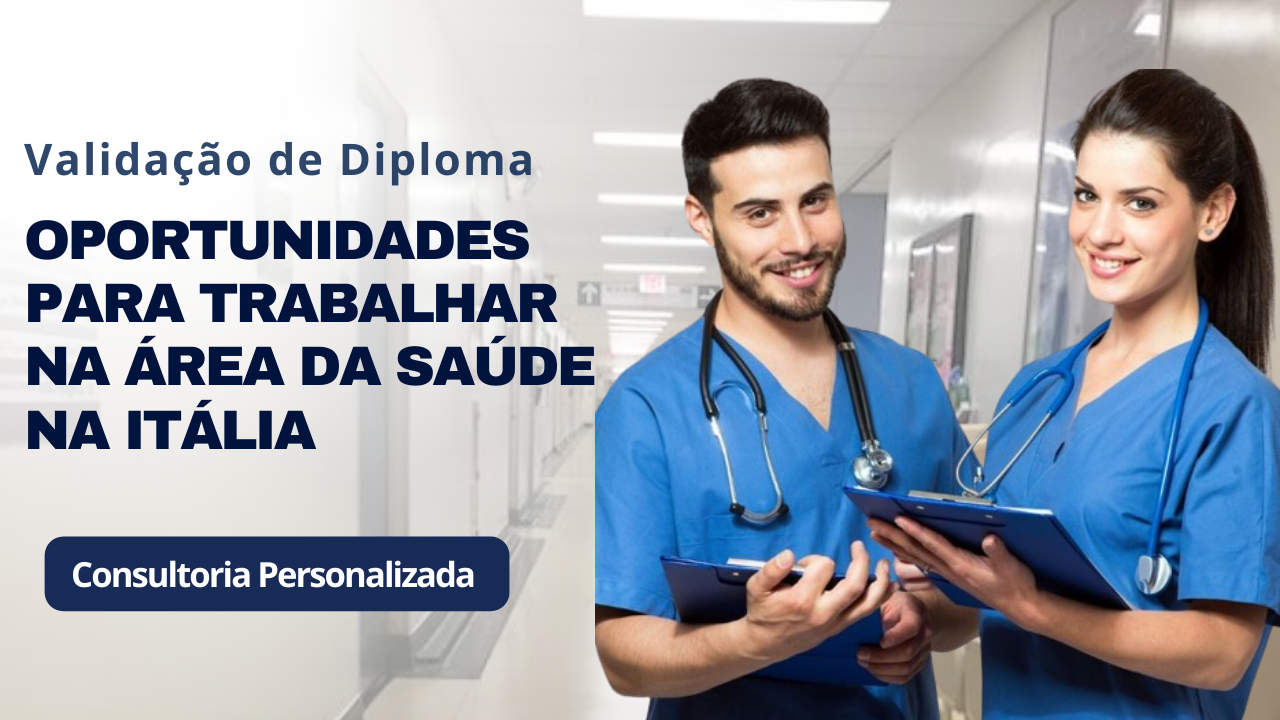

Em um passo que reverbera como um novo sopro na paisagem do tratamento oncológico, a AIFA aprovou a combinação terapêutica destinada a pacientes com NSCLC portadores da mutação BRAF V600E. A notícia foi recebida com orgulho por Pierre Fabre, cujo representante, De Vecchi, enfatizou a prioridade da empresa em acelerar o acesso e estreitar laços com a comunidade científica.

“Nosso primeiro objetivo é disponibilizá-la o mais rapidamente possível e de colaborar com a comunidade científica para fazer em modo que os pacientes possam beneficiar-se ao máximo dessa terapia”, afirmou De Vecchi. A declaração, traduzida para o cenário italiano e agora para a sensibilidade do leitor brasileiro, reflete a intenção de transformar a aprovação regulatória em benefício concreto e imediato — algo que, na prática clínica, é como semear logo após o inverno, quando a terra está pronta para a colheita.

Pierre Fabre sublinha que a liberação pela AIFA não é um ponto final, mas um compromisso contínuo. Isso inclui suporte ao acesso, diálogo com sociedades científicas e iniciativas para esclarecer critérios de elegibilidade e manejo de possíveis efeitos, sempre com atenção humana e prática. Em linguagem simples: a aprovação regula o caminho; caberá à comunidade transformá-lo em cuidado real.